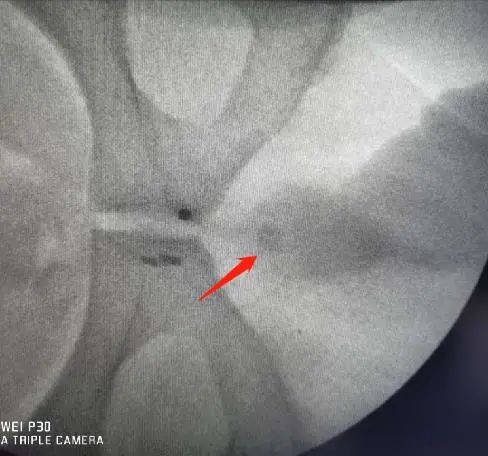

碎石科报告三: 体外碎石治疗尿道膜部结石 近日,来自我县河凤桥乡的一位男性患者,突发排尿困难来我院泌尿外科就诊,王昌国主任诊断为尿道结石,遂推荐患者到碎石科进一步治疗。 影像显示患者的结石位于尿道膜部,碎石科彭仁焕主任、蒋朋医师综合评估认为,如使用尿道探子将结石推回膀胱,按膀胱结石治疗,成功的可能性极小且风险和患者的痛苦都比较大,经过与常驻我院的郑州大学第二附属医院专家王友志教授会诊交流后,认为可以首选尝试体外冲击波碎石。 在征得患者同意后,遂为其采取体外冲击波碎石治疗,整个过程十分顺利,术后立马看见结石随尿液排出,患者排尿困难的现象也立刻得到缓解。 一周后,患者特地来碎石科为团队送来了一面锦旗以表感激之情! 尿道结石可引起排尿困难,给患者造成极大的痛苦,最早期的治疗办法是使用尿道探子将结石推回膀胱,按膀胱结石处理,若不能推回膀胱则做尿道切开取石术,靠近尿道外口舟状窝处结石可用弯钳夹出来。后来,随着腔镜碎石技术的发展,大多都采用微创的办法即膀胱尿道镜下碎石取石术。自从体外冲击波碎石机问世后,便有众多同行尝试体外碎石,但是该部位结石定位困难,并且有权威报道体外碎石术后可能会引起尿道狭窄。但是,王友志教授认为,只要碎石机设备允许,体位摆放得当,定位精确,冲击波能量、频率、次数把握恰当,尿道狭窄等并发症完全可以避免,尿道结石行体外碎石仍然是最佳选择。 体外冲击波碎石术近年来逐渐普及,患者无需开刀、无伤口、损伤小且碎石彻底、复发率低,较药物排石,手术取石有独特的优势,已经成为泌尿系结石的常规治疗方法。该项新技术在我院的落地运用为广大泌尿系结石患者提供了更安全高效的治疗方案,更好的满足人民群众在“家门口”享受优质医疗服务的需求,让患者省时省钱省心。 王友志 郑州大学第二附属医院主任技师 教授 中国体外冲击波碎石治疗安全共识执笔专家和专家组成员 医学院校体外冲击波碎石规培教材编者 德国多尼尔碎石机2020温暖人心奖和最佳导师奖获得者 中国研究型医院体外冲击波学会全国委员 中国尿石联盟华南基地河南中心委员 专业特长:擅长体外冲击波碎石,体外物理振动排石和经直肠超声引导系统性前列腺穿刺活检术。特别善于根据影像学图像,分析结石成分,判断结石脆性,评估冲击波碎石疗效,把握碎石剂量,避免和减少治疗引起组织损伤。尤其对于复杂性泌尿系结石术后辅助物理振动排石治疗具有独到之处,与腔内泌尿外科手术配合,成为泌尿系结石治疗的真正“黄金搭档”。 健康就诊地址:门诊二楼东 健康咨询电话:0376——7973081